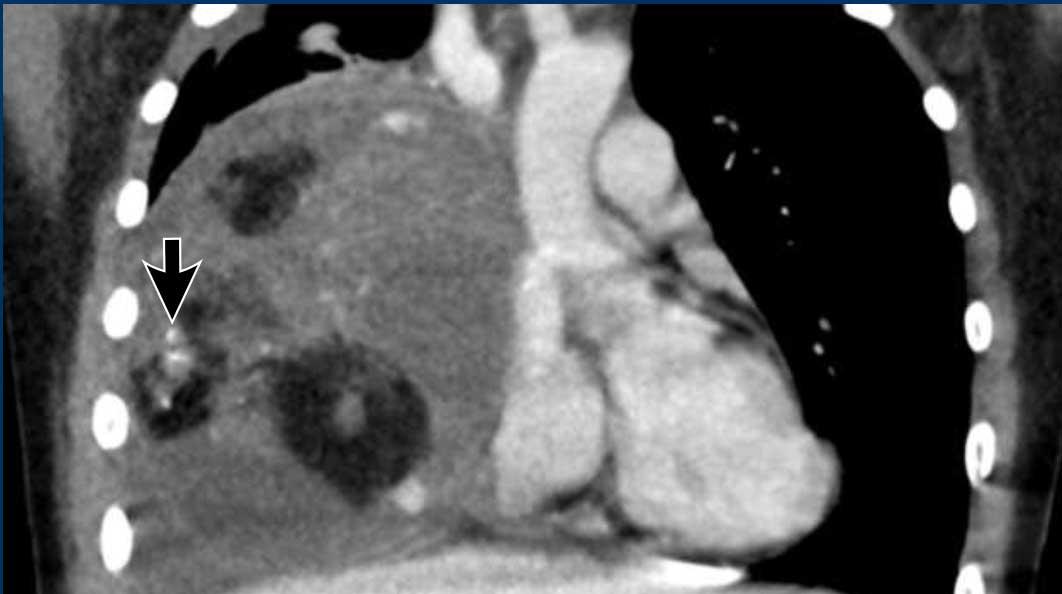

Các hình ảnh này của một nam giới 71 tuổi.

Trên CT ngực, tình cờ phát hiện một khối ở tuyến ức.

Hãy phân tích các hình ảnh. Nhận định của bạn là gì?

Hình ảnh

Một phần tổn thương có ngấm thuốc cản quang và có một số vôi hóa, có thể nằm ở thành nang.

Khi một tổn thương tuyến ức có thành phần đặc, nguyên tắc là… “khi còn nghi ngờ, hãy phẫu thuật cắt bỏ”.

Tổn thương đã được phẫu thuật cắt bỏ dựa trên kết quả CT và kết quả giải phẫu bệnh cho thấy đây là u tuyến ức dạng nang.